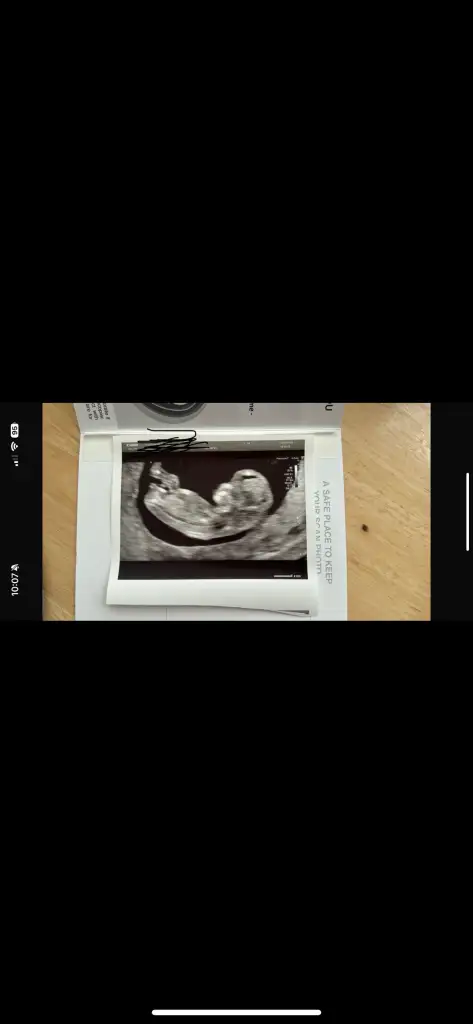

İyi Akşamlar arkadaşlar bende klübe yeni katıldım 13 haftalık bebegim anlayan arkadaşlar cinsiyetine bakabilirmi doktor kız benziyor dedi ama net birşey söylemedi

Ayy banada bakarmısınız çok merak ediyorum daha belli değil dedi doktor